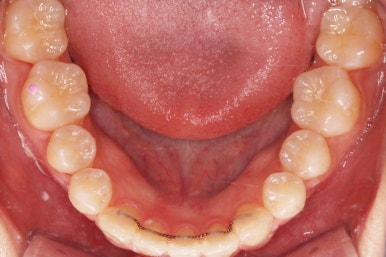

부산교정 키다리아저씨치과에서 결손치아 부분을 임플란트 하지 않고 치아교정을 통해서 개선한 이번 환자분의 치료를 마무리한 사진입니다.

치열은 가지런해졌고, 틈새는 없이 마무리되었습니다. 아랫니가 3개이지만 마치 4개인 것처럼 마무리하였고, 따라서 위~아래 치열의 중앙도 거의 맞게 마무리하였습니다.

(한 쪽은 송곳니를 앞니 대신 사용해야 했어서 크기 문제로 완벽히는 중앙을 맞추기 힘듭니다.)